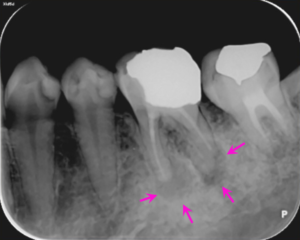

治療前

左下の奥歯の痛みの主訴でご来院しました。

左下6番の歯の根の先に炎症があり膿が出ていたので、根の治療(根管治療)を提案し、患者様の合意を頂き治療をすすめることになりました。

左図のレントゲン写真では根の先に炎症があり骨が溶けている部分があります(矢印部) 。